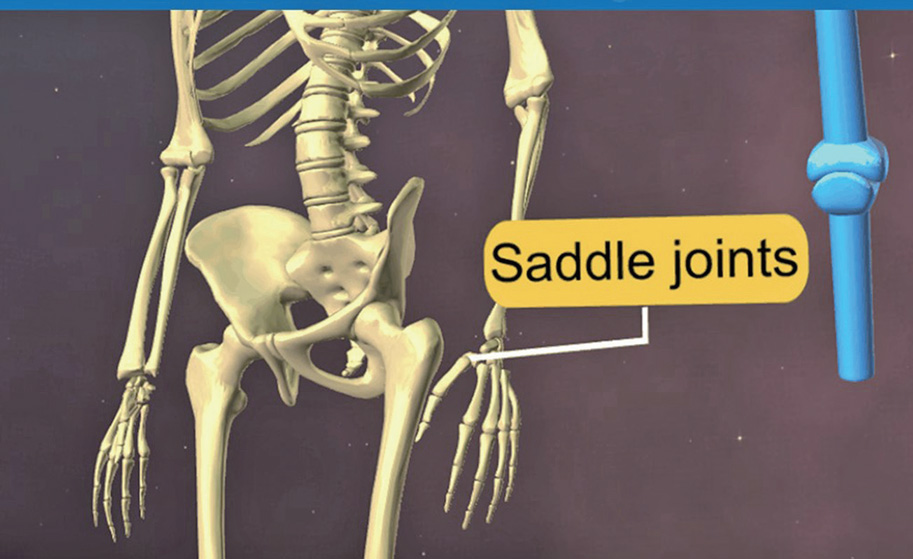

- 가동관절⑤ 안장관절